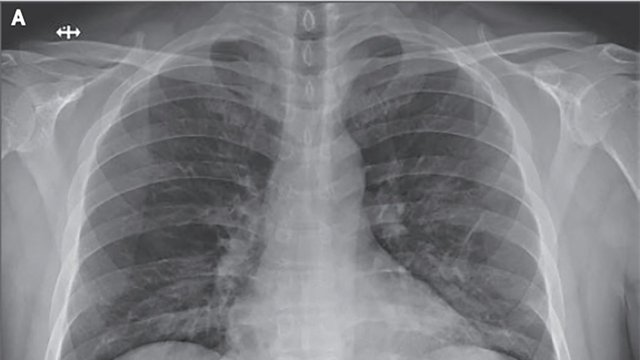

Пацієнти, які вилікувалися від смертельної коронавірусної інфекції можуть страждати від погіршення функції легень і задухи при швидкій ходьбі.

Як повідомив глава центру інфекційних захворювань лікарні Принцеси Маргарет Оуен Цзен, двоє або троє з них вже не здатні робити те, що могли робити раніше. "Вони задихаються при швидкій ходьбі. У деяких пацієнтів може спостерігатися зниження функції легень на 20-30% (після одужання)", – йдеться в повідомленні.

За словами Цзен, ці пацієнти пройдуть подальше обстеження, щоб визначити, наскільки у них ослаблена легенева функція, також їм буде призначена фізіотерапія для зміцнення легенів. Аналіз результатів комп'ютерної томографії легенів дев'яти пацієнтів, які проходили лікування, виявив ознаки, схожі з симптомом "матового скла", що свідчить про пошкодження внутрішніх органів.